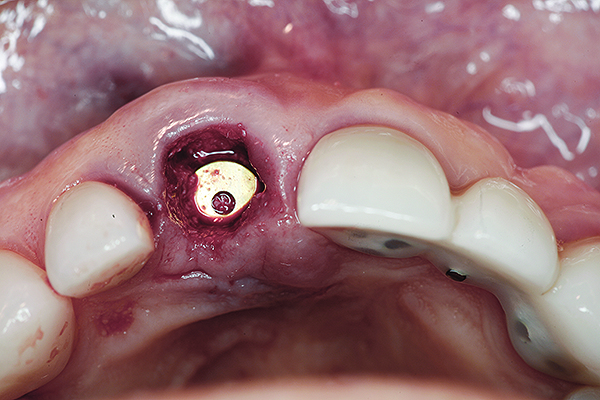

Fig 7. Occlusal view of the implant after insertion.

Figure 7

Fig 8. After placement of a cover screw, bone graft material was packed into the gap between the implant and the buccal wall.

Figure 8